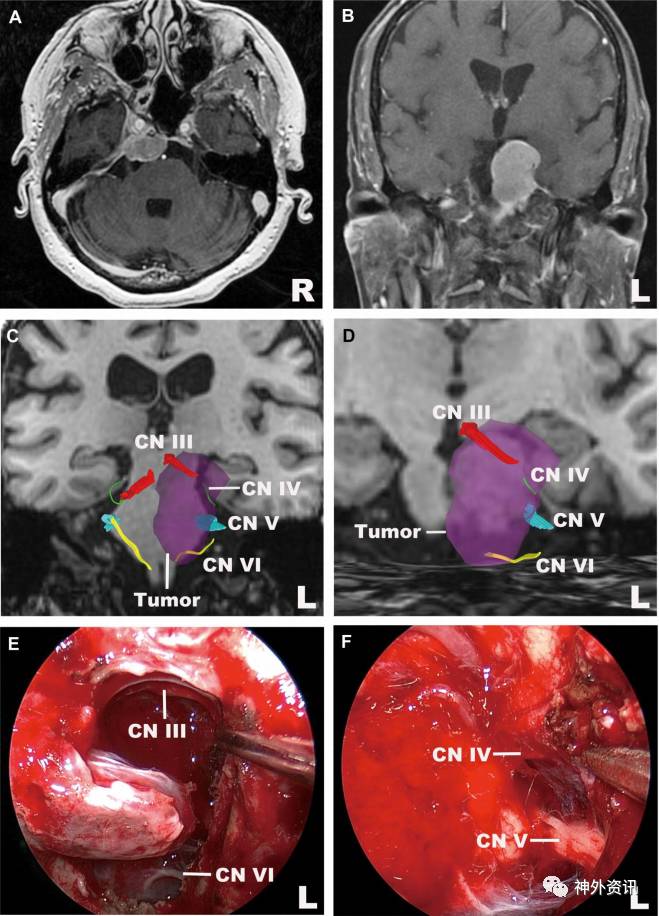

图11. 岩斜区脑膜瘤。A. MRI轴向位;B. MRI冠状位;C.动眼神经、滑车神经、三叉神经和外展神经(冠状位),以及动眼神经和外展神经与肿瘤的毗邻关系;D.左侧动眼神经和外展神经放大图(冠状位);E、F.术中图像显示,纤维束重建图与术中所见一致。